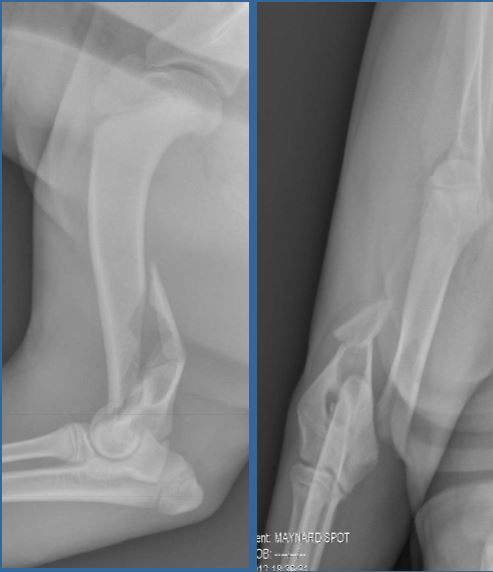

4 year old NM Burmese, 5kg

Unknown trauma yesterday

Classify and assess fracture, and give repair options

Luxation of the radial head

and

Montaggia fracture of the ulna

Repair: ASAP - IM pin in ulna + Cerclage wire around radius